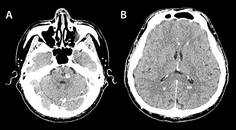

Management of Vein of Galen Thrombosis With Mechanical Thrombectomy